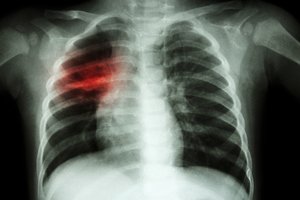

Tuberkuliozė plinta oro lašeliniu būdu, t. y. tuberkuliozės mikobakterijos patenka į orą, kai plaučių tuberkulioze sergantis žmogus kalba, kosti, čiaudo, spjaudo skreplius. Žmogus užsikrečia įkvėpęs užkrėsto tuberkuliozės mikobakterijomis oro.

Suaugusieji tiriami rentgenologiškai, o vaikams atliekamas tuberkulino mėginys. Siuntimus pasitikrinti sveikatą pas šeimos gydytoją, asmenims, kurie kolektyve galėjo turėti artimą sąlytį su sergančiu atvira tuberkulioze asmeniu, išduoda NVSC specialistai. Šeimos narių ištyrimą dėl tuberkuliozės organizuoja ligą nustatęs gydytojas pulmonologas.